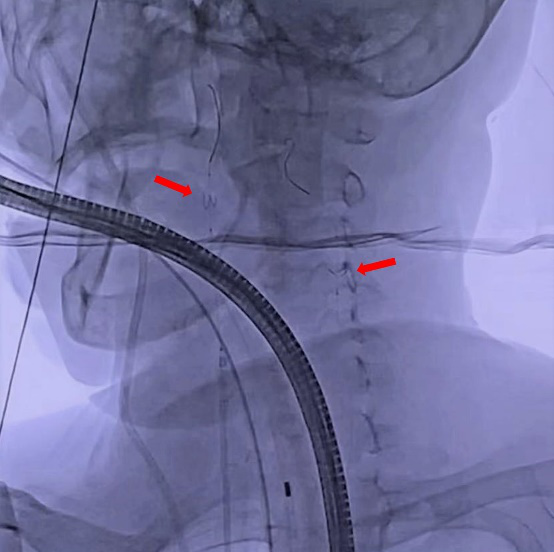

沿动静脉轨道送INOUS二尖瓣扩张球囊至二尖瓣口,依次以18mm、19mm、20mm、22mm扩张(图4),术后心超测得二尖瓣瓣口面积2.2cm2,彩色多普勒示轻微二尖瓣反流(图5)

图4. 二尖瓣球囊扩张

扩张效果满意后,成功回收左右颈内动脉内滤器,其内见血栓(图6)。术后苏醒即刻,患者无四肢活动障碍及言语障碍等脑梗征象。术后第二日即下床活动,心衰症状较前明显改善,无器官栓塞表现。患者病情得到有效治疗。

图6. 回收颈动脉滤器